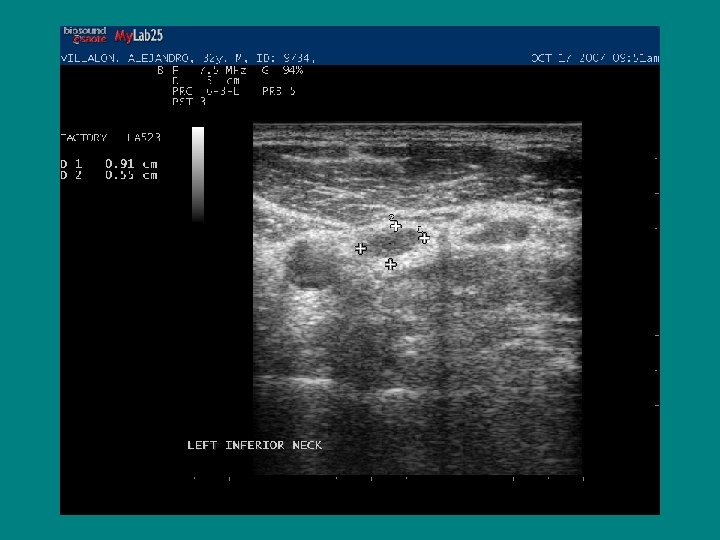

Case 2 Ø 32 y/o male with Papillary thyroid cancer 1999 ØNTT pathology showed 4. 5 x 2. 6 x 2. 0 cm mass ØMulti focal ØMultiple lymph nodes positive, bilaterally ØT 3 N 1 B MX

NOW WHAT ? • Role of ultrasound

WHERE AND WHEN DOES RECURRECE OCCUR • 79 % RECURRENCE OCCURS IN THE NECK • 74 % OF RECURRENCE IS IN THE LYMPH NODES • TIME TO RECURRENCE USUALLY VARIES, SOME CASES RECUR AT 7 -10 YEARS AMERICAN JOURNAL OF MEDICINE 1997 VOL 97 MAZZAFERI ET AL

HIGH SERUM THYROGLOBULIN NEGATIVE IMAGING ! LIKELY DUE TO A) CERVICAL LYMPH NODE METASTASIS B) METASTASIS TOO SMALL TO BE SEEN ON Dx. WBS OR Rx. WBS

• Higher Thyroglobulin level means a higher chance of detection of mets/mass • In patients with TG > 5 after rh. TSH ultrasound picked up neck masses/mets in 67 % patients

AP/T 0. 79/1. 45= 0. 54 !